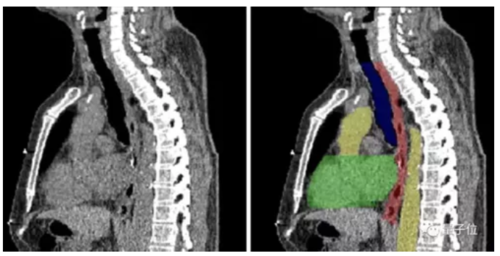

图像分割,顾名思义,就是将图像切分为多个区域,来简化或改变图像的表现形式,从而让图像变得更加容易解读和分析。

目前,图像分割技术用在了肿瘤和其他病理位置定位、组织体积测量、解剖学研究、计算机辅助手术、治疗方案制定以及临床辅助诊断等多个细分领域。

图像分割的实现方式也不难理解——以图像中的自然边界,例如物体轮廓、线条等,将图像切分为多个区域。

在计算机中,是对图像中的每个像素加上标签,并认为具有相同标签的像素有着某种共同视觉特性,从而来实现分割。

传统中有基于聚类、阈值、边缘、区域等特征的方法。但随着AI技术的发展,基于深度学习的方法效果出众,超过人类,成为最广泛的应用。

这其中,全卷积网络(Fully Convolutional Network, FCN)、U-net 和 V-net 是常见的几种基于深度学习的图像分割方法。

但在医疗领域中,应用最为广泛的则是U-net 。需要分割的图像有其独特性,大多数情况下是针对一个指定器官的成像,而非全身。

器官本身结构比较固定,语义信息并非特别丰富。

所以高级语义信息和低层级特征就显得重要,而 U-net 的 U 型结构和跳跃连接在这种场景中,可以发挥出更大作用。

近年来,U-net 在医学影像 分割领域良好的应用效果,已在很多部署中得到充分了证明。

良好的图像分割模型,能有效帮助医疗机构提高医学影像判读效率,进而增强临床诊疗能力、提升疾病治愈率以及减少病患等待时间,弥补因医疗机构影像科资源缺乏带来的多种问题。

但医疗领域的图像分割对时效性要求更高。

通常情况下,留给病患的黄金诊疗窗口往往只有数十分钟。因此,如果图像分割 AI 应用的推理效率不够高,就有可能延误宝贵的抢救时间。

这就决定想要将图像分割应用到真正的医疗场景中,一方面需要基于不同的图像分割类型对模型进行优化,另外一方面则需要强大稳定的计算能力来完成推理。

怎么进一步落地?英特尔提供了工具,比如OpenVINOTM工具套件以及至强处理器系列产品等等, 能够在在保证 U-net 模型高准确率的同时,推理时间大幅降低85%。

在报告中不仅给出了具体的使用方法,也放出了不少已经落地的案例,比如东软的eStroke溶栓取栓影像平台,西门子的心腔检测和量化模型等等。